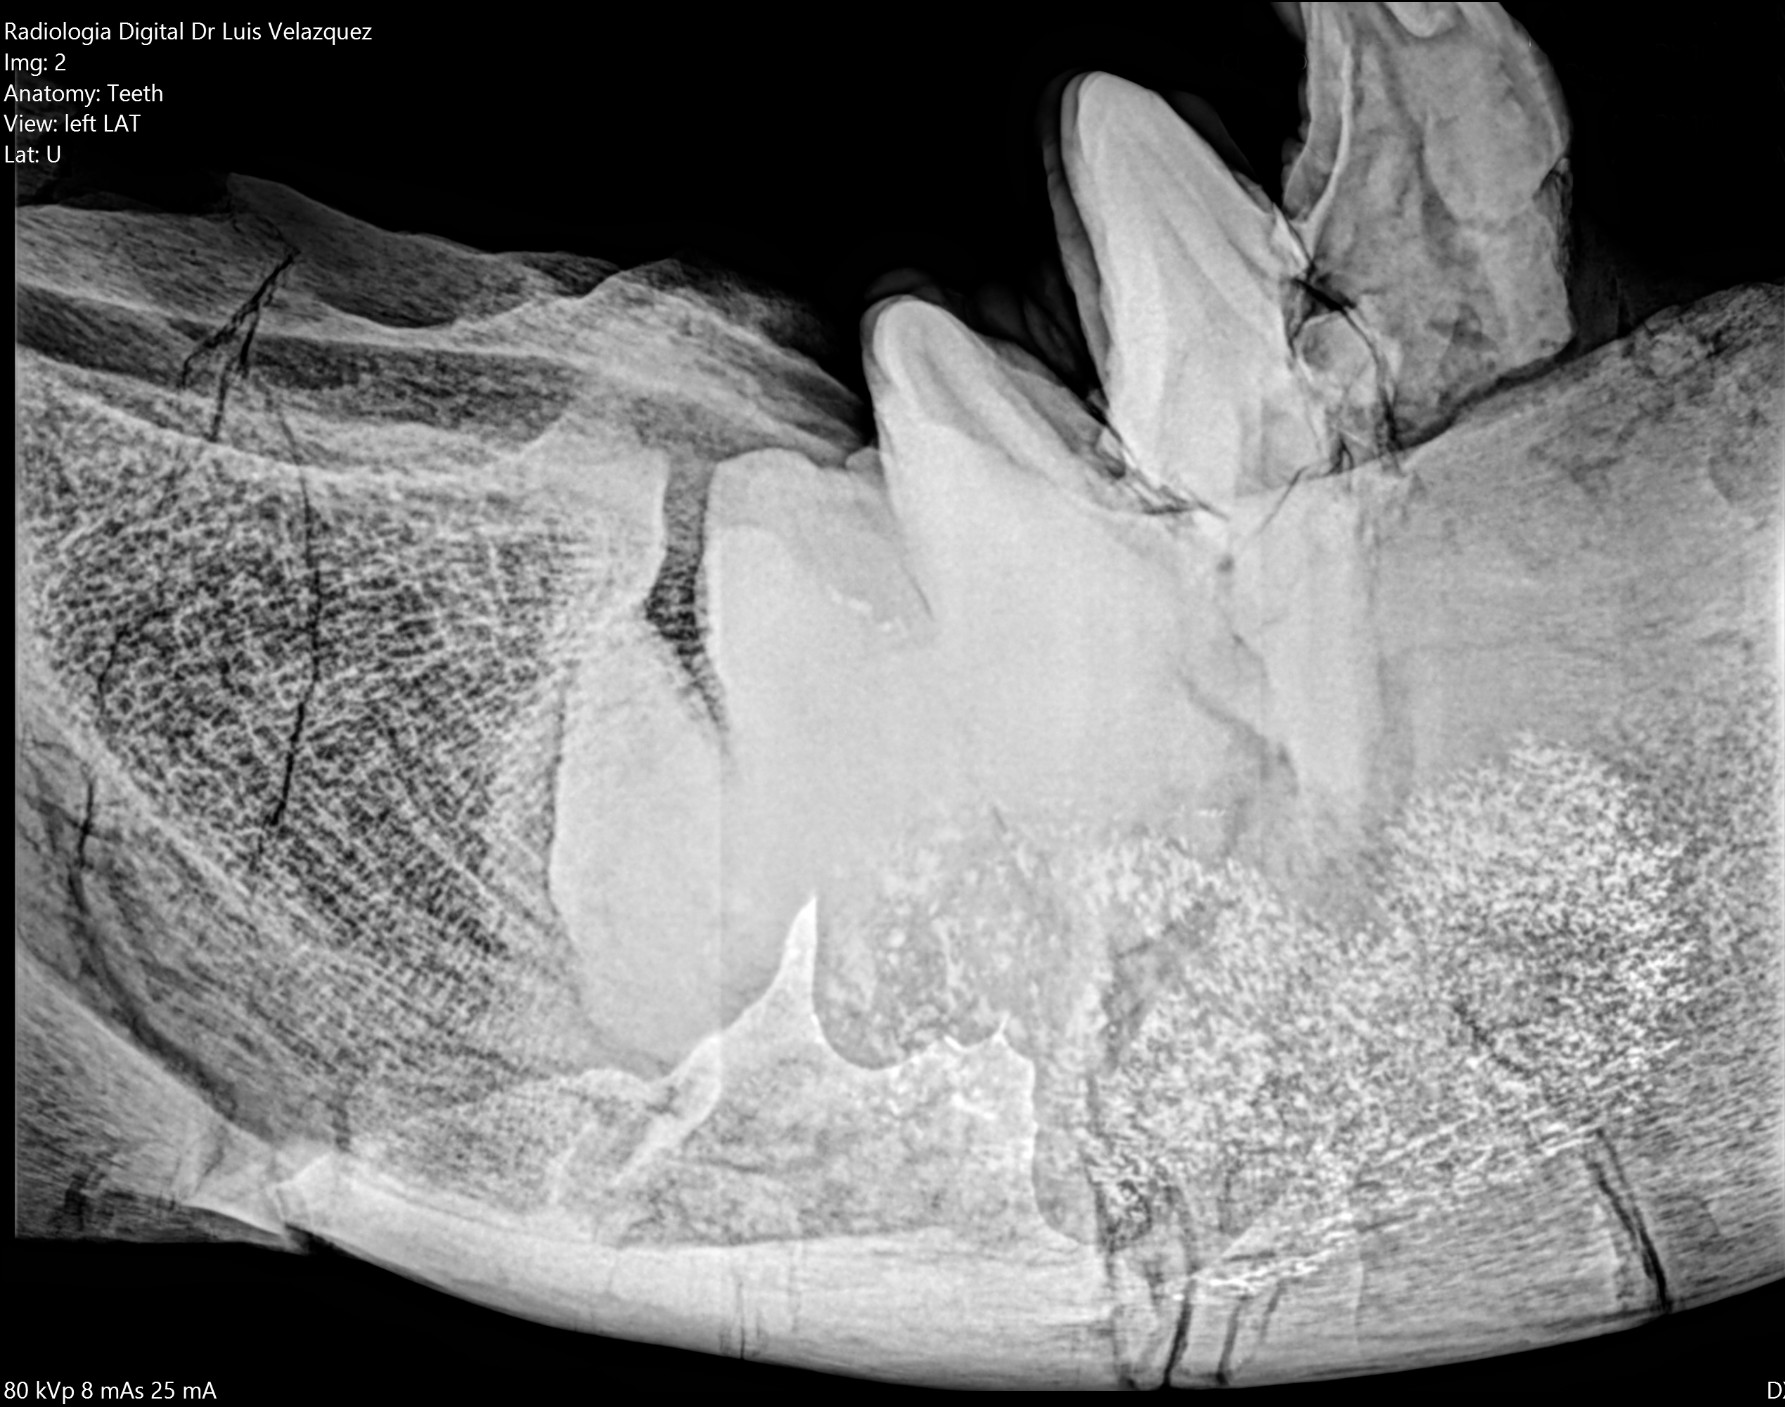

Cambios Térmicos en las Extremidades de Caballos,

Asociados a Golpes y su Evaluación por Termografía.

Los caballos de salto, en competencia, pueden derribar obstáculos y lastimarse. Si se golpean, no siempre claudican. Considerando al calor como un signo de inflamación, se evaluaron los cambios térmicos de 6 áreas de las extremidades torácicas y pelvianas de 23 caballos de salto en nivel de competencia de 1.05 a 1.60 m de altura, por medio de termografía durante 4 días de competencia (N=2208 áreas).